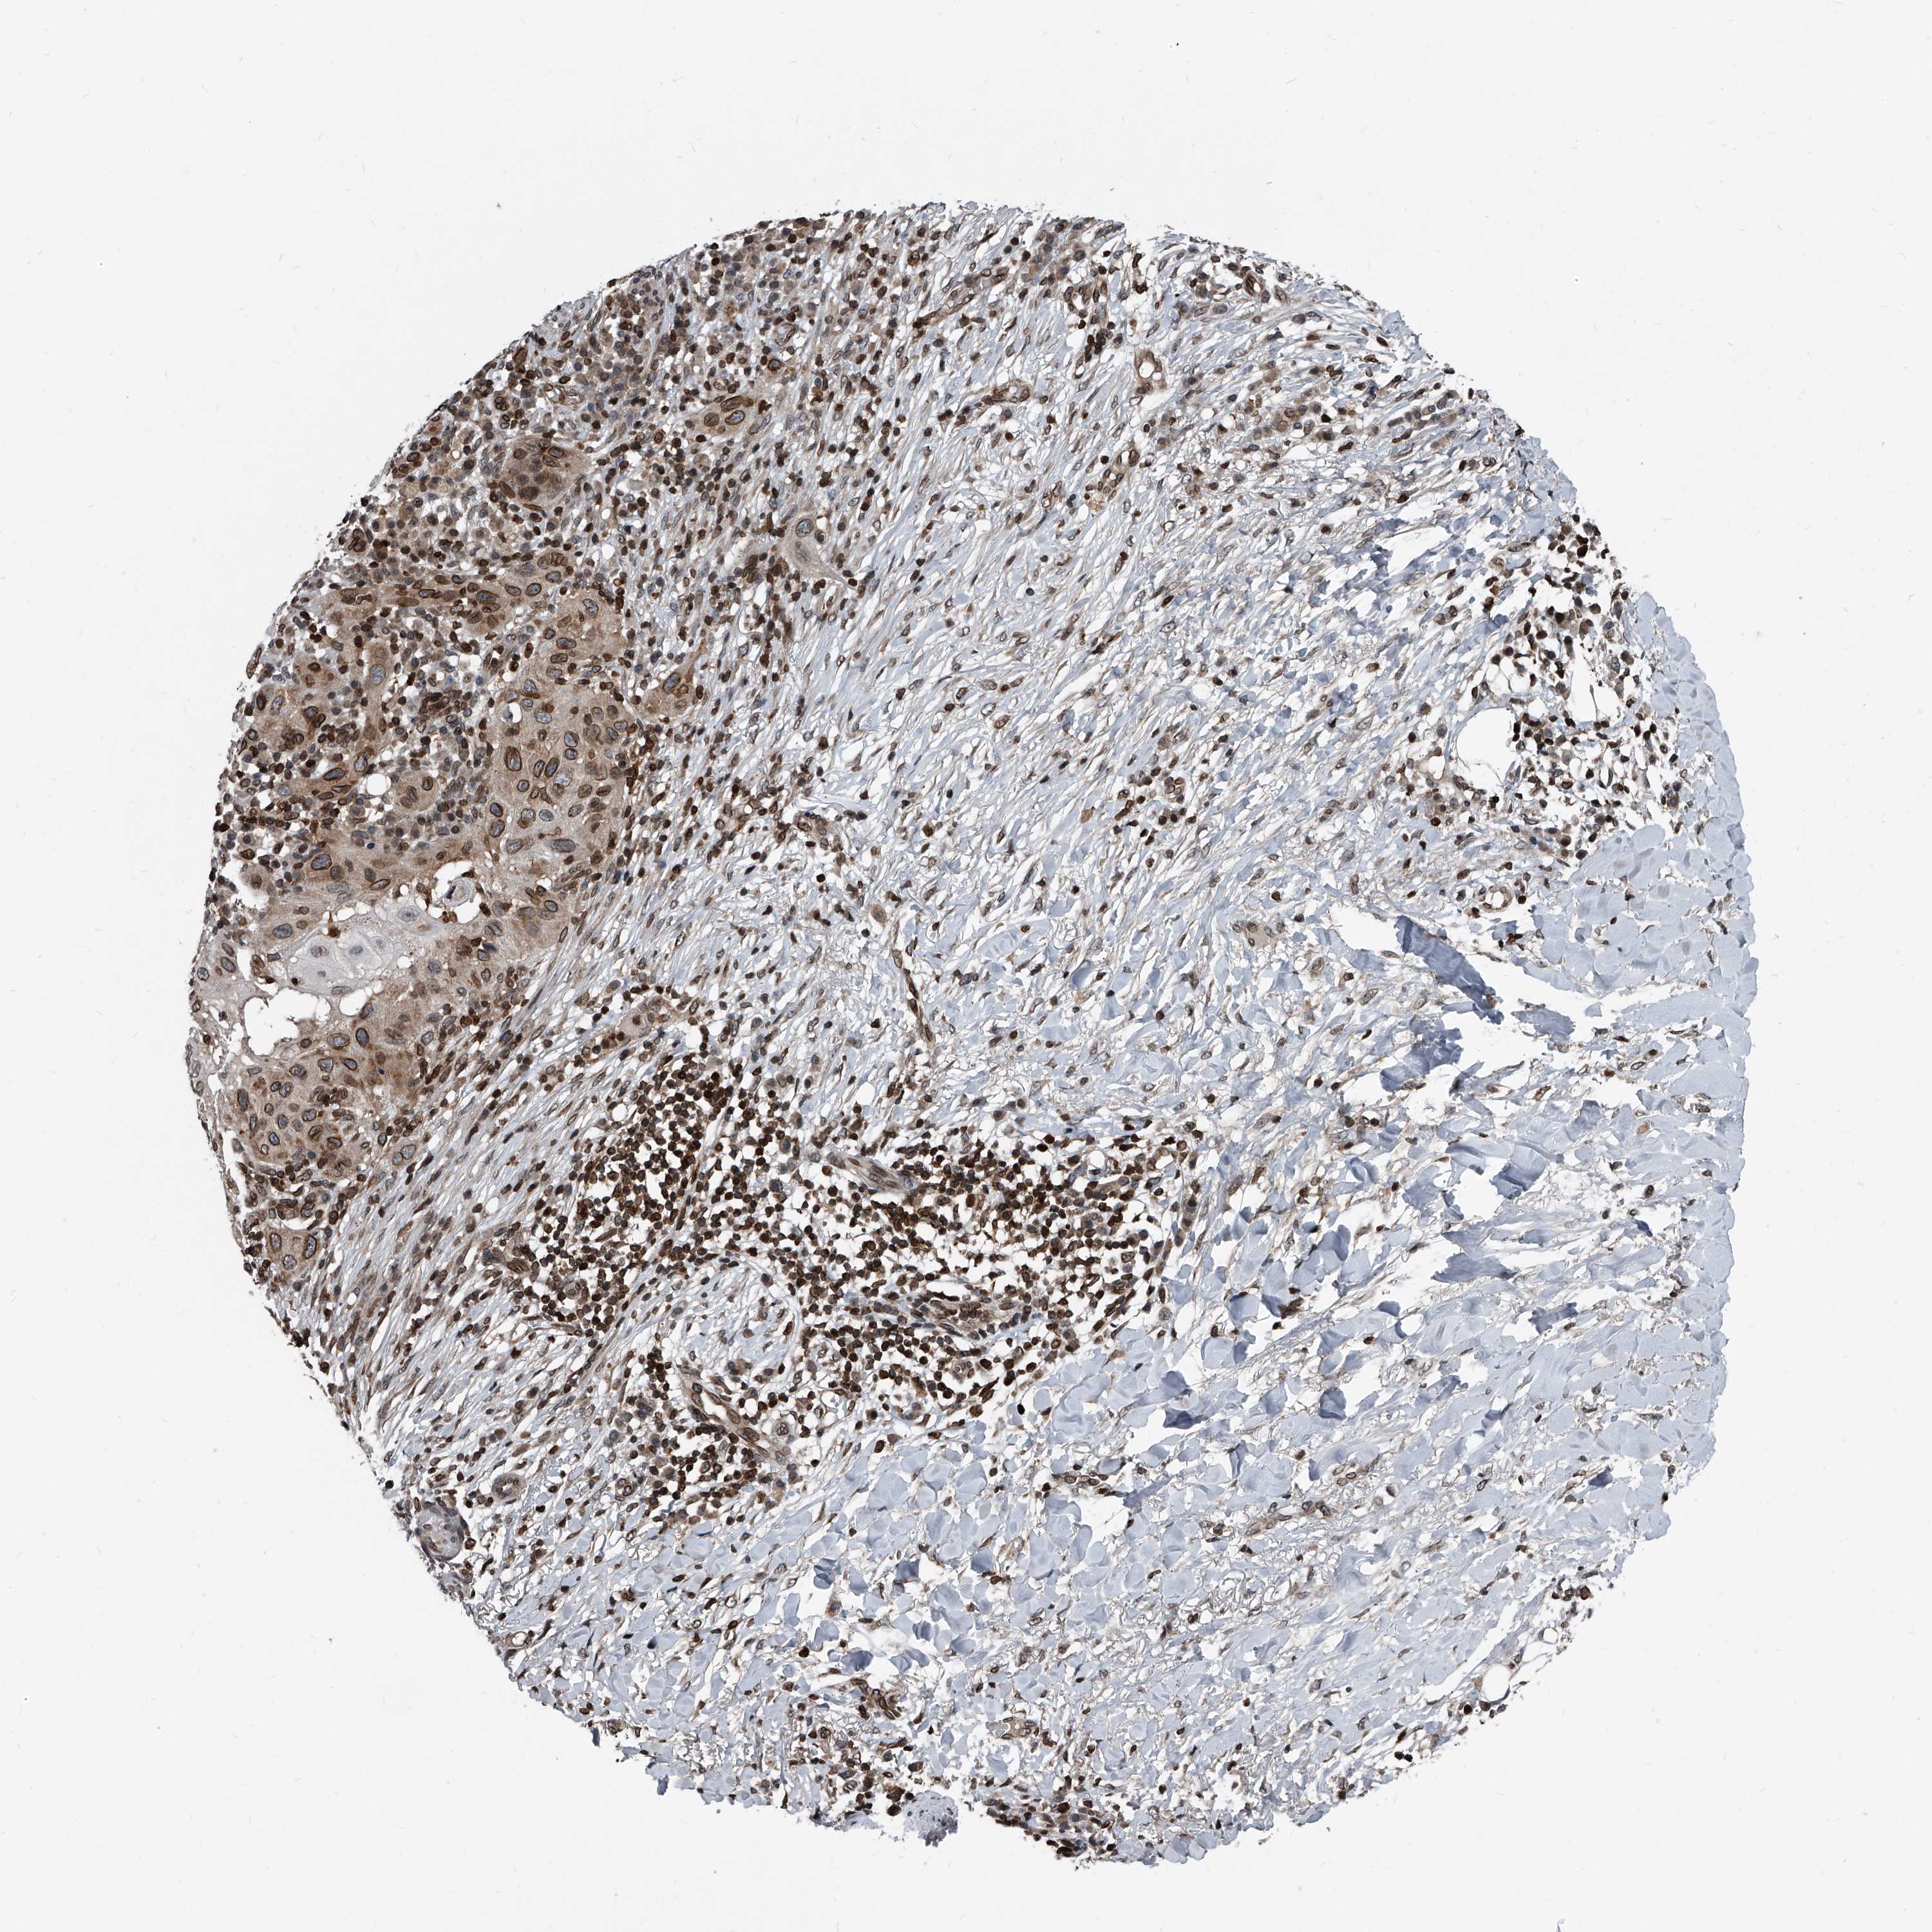

CANCER SKIN CANCER Show tissue menu

Basal cell and squamous cell cancer

SKIN CANCER - Protein expressioni

A mouse-over function shows sample information and annotation data. Click on an image to view it in a full screen mode. Samples can be filtered based on level of antibody staining by selecting one or several of the following categories: high, medium, low and not detected. The assay and annotation is described here.

Antibody stainingi

Antibody staining in the annotated cell types in the current human tissue is reported as not detected, low, medium, or high, based on conventional immunohistochemistry profiling in selected tissues. This score is based on the combination of the staining intensity and fraction of stained cells.

Each image is clickable and will lead to virtual microscopy that enables deeper exploration of all samples and also displays staining intensity scores, fraction scores and subcellular localization as well as patient and tissue information for each sample.

Antibody HPA029619

Antibody HPA029621

Staining

High

Medium

Low

Not detected

Intensity

Strong

Moderate

Weak

Negative

Quantity

>75%

75%-25%

<25%

None

Location

Nuclear

Cytoplasmic/membranous

Cytoplasmic/membranous,nuclear

Basal cell carcinoma

Squamous cell carcinoma, NOS

Squamous cell carcinoma, metastatic, NOS